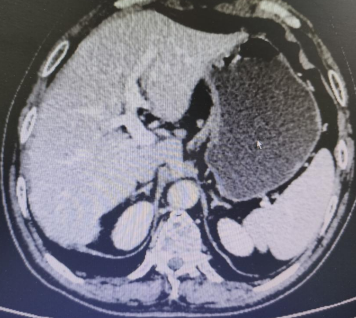

Abdominal CT films from March 3, 2020 (2 images)